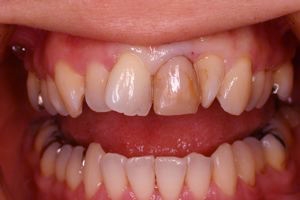

術前口腔内(正面観)

術前